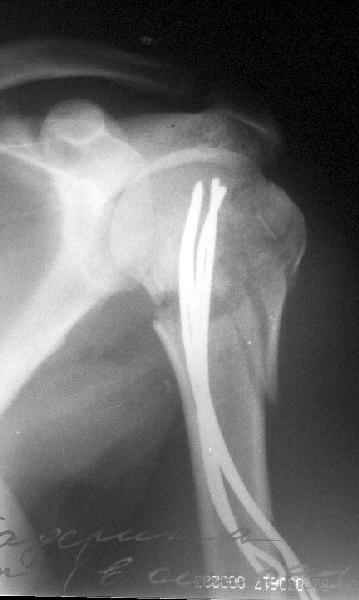

Клинические снимки - 3 недели после операции

Посылаю послеоперационные Рг граммы.

Спасибо за поздравления:-))

Я и сам доволен результатом. В предпоследнем письме я кратко описал ход операции - закрыто репонировать не удалось( 2 недели с момента травмы и 1 неделя после неудачной репозиции) после удаления пучков спиц, пришлось сделать - 2см разрез на уровне перелома и с помощью периостального элеватора (золотое правило механики) *одеть* головку на дистальный отломок.

Спицы проводил через старые отверстия, вращая пучок импактором- направителем при его введении в головку.